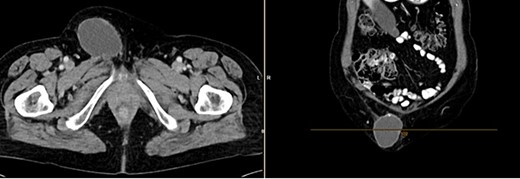

The CT of the abdomen showed a highly suspicious malignant mass in the left groin area (Fig 3). Additionally, nearby satellite lesions were detected, interpreted as lymph nodes. During a more thorough physical examination, a hazelnut-sized, highly suspicious malignant lesion was identified on the glans penis. Upon detailed anamnesis, the patient reported a previous circumcision surgery with carcinoma detection.

Finding from CT of the abdomen: highly suspicious malignant mass in the left groin area, with nearby satellite lesions, DD lymph nodes.